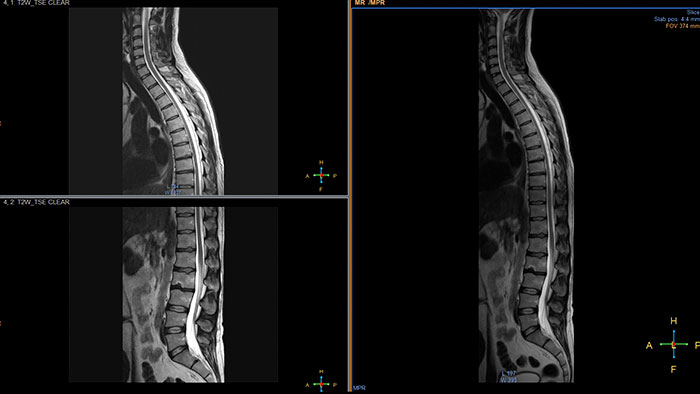

Automatic review of total body MR data

MR MobiView, an option within the Multi Modality Viewer, automatically combines "stitches“ images from multiple acquisitions of the same examination to create one overall volume.